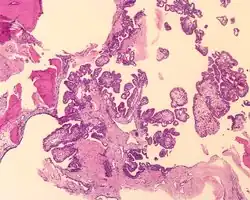

An intermediate power image of an endolymphatic sac tumor with bone (upper left).

Tumors range from several millimeters up to 10 cm, with larger tumors more frequently seen in older patients. If the tumor is bilateral, it is almost always seen in a VHL patient. The tumor destroys the mastoid air spaces and extends into the middle ear and/or posterior cranial fossa.[1][3]

A high power image of an endolymphatic sac tumor showing clear cytoplasm in cuboidal cells lined up along papillae.

The microscopic appearance shows an unencapsulated, destructive growth, remodeling and invading bone. The tumor is arranged as simple, broad, non-complex papillary projections without large cystic spaces. The spaces are often fluid filled, have extravasated erythrocytes and/or inspissated material. The cells are cuboidal, usually single layered along the papillary structures, showing indistinct cell borders. The nuclei are round and hyperchromatic.[1][3][10][11]